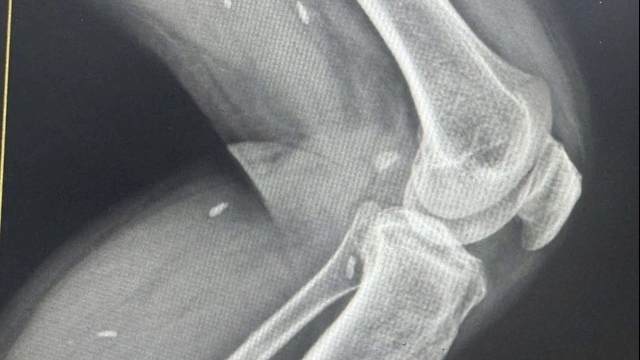

Bệnh nhân bất tỉnh ngay tại chỗ. Trên người bệnh nhân có nhiều vết thương vùng đầu, tay và chân. Đặc biệt phần đùi phải của nam bệnh nhân bị biến dạng, dập nát, máu không ngừng chảy, gãy hở 1/3 trên xương đùi phải.

Da đầu vùng thái dương đỉnh trái có vết thương rách dài 6cm, sưng nề. Huyết áp và mạch không đo được. Da niêm mạc nhợt nhạt, đầu chi lạnh. Không thấy có biến dạng vùng lồng ngực, thành bụng không có phản ứng, không thấy chảy máu và dịch từ tai và mũi. Bệnh nhân ngừng tuần hoàn ngoại viện, sốc mất máu, đa chấn thương.

Kết quả, sau 3 phút ngừng tuần hoàn lần thứ nhất, bệnh nhân bắt đầu có nhịp tim nhưng yếu ớt. Tiếp đến, cả ê-kíp cấp cứu đã nhanh chóng đưa bệnh nhân di chuyển sang khoa Chẩn đoán hình ảnh chụp CT sọ não, cột sống cổ, ngực, bụng và đưa thẳng lên phòng mổ cấp cứu.

20h20, bệnh nhân được đưa lên phòng mổ cấp cứu lần 2. Dù trăn trở nhưng các bác sĩ vẫn phải cắt cụt 1/3 trên đùi phải của người bệnh, tiếp tục truyền máu khẩn cấp.